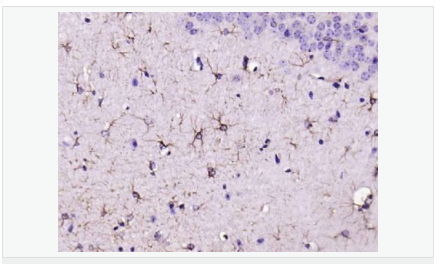

| 產(chǎn)品應用 | WB=1:500-2000 ELISA=1:5000-10000 IHC-P=1:200-1000 IHC-F=1:200-1000 Flow-Cyt=1μg/Test ICC=1:100 IF=1:200-800 (石蠟切片需做抗原修復) not yet tested in other applications. optimal dilutions/concentrations should be determined by the end user. |

| 產(chǎn)品介紹 | This gene encodes one of the major intermediate filament proteins of mature astrocytes. It is used as a marker to distinguish astrocytes from other glial cells during development. Mutations in this gene cause Alexander disease, a rare disorder of astrocytes in the central nervous system. Alternative splicing results in multiple transcript variants encoding distinct isoforms. [provided by RefSeq, Oct 2008] Function: GFAP, a class-III intermediate filament, is a cell-specific marker that, during the development of the central nervous system, distinguishes astrocytes from other glial cells. Subunit: Interacts with SYNM. Isoform 3 interacts with PSEN1 (via N-terminus). Subcellular Location: Cytoplasm. Note=Associated with intermediate filaments. Tissue Specificity: Expressed in cells lacking fibronectin. Post-translational modifications: Phosphorylated by PKN1. DISEASE: Defects in GFAP are a cause of Alexander disease (ALEXD) [MIM:203450]. Alexander disease is a rare disorder of the central nervous system. It is a progressive leukoencephalopathy whose hallmark is the widespread accumulation of Rosenthal fibers which are cytoplasmic inclusions in astrocytes. The most common form affects infants and young children, and is characterized by progressive failure of central myelination, usually leading to death usually within the first decade. Infants with Alexander disease develop a leukoencephalopathy with macrocephaly, seizures, and psychomotor retardation. Patients with juvenile or adult forms typically experience ataxia, bulbar signs and spasticity, and a more slowly progressive course. Similarity: Belongs to the intermediate filament family. SWISS: P14136 Gene ID: 2670 Database links: Entrez Gene: 2670 Human Entrez Gene: 14580 Mouse Omim: 137780 Human SwissProt: P14136 Human SwissProt: P03995 Mouse Important Note: This product as supplied is intended for research use only, not for use in human, therapeutic or diagnostic applications. 星形膠質(zhì)細胞標志物 (Astrocyte Marker) GFAP是一個56kDa的中間絲蛋白(intermediate filament,IF),在中樞神經(jīng)系統(tǒng)發(fā)育期是一個特異性的標志物,以區(qū)別星形細胞和其它膠質(zhì)細胞。GFAP表達在皮層和海馬,急、慢性皮質(zhì)酮治療時表達減少。 GFAP可以和人、大鼠、小鼠的GFAP反應,在正常和腫瘤性的星形膠質(zhì)細胞陽性表達,而神經(jīng)節(jié)細胞、神經(jīng)元、成纖維細胞、少突膠質(zhì)細胞和這些細胞來源的腫瘤細胞陰性表達,主要用于星形膠質(zhì)瘤等中樞神經(jīng)系統(tǒng)腫瘤的診斷和鑒別診斷,GFAP的缺乏可導致AD病。 |